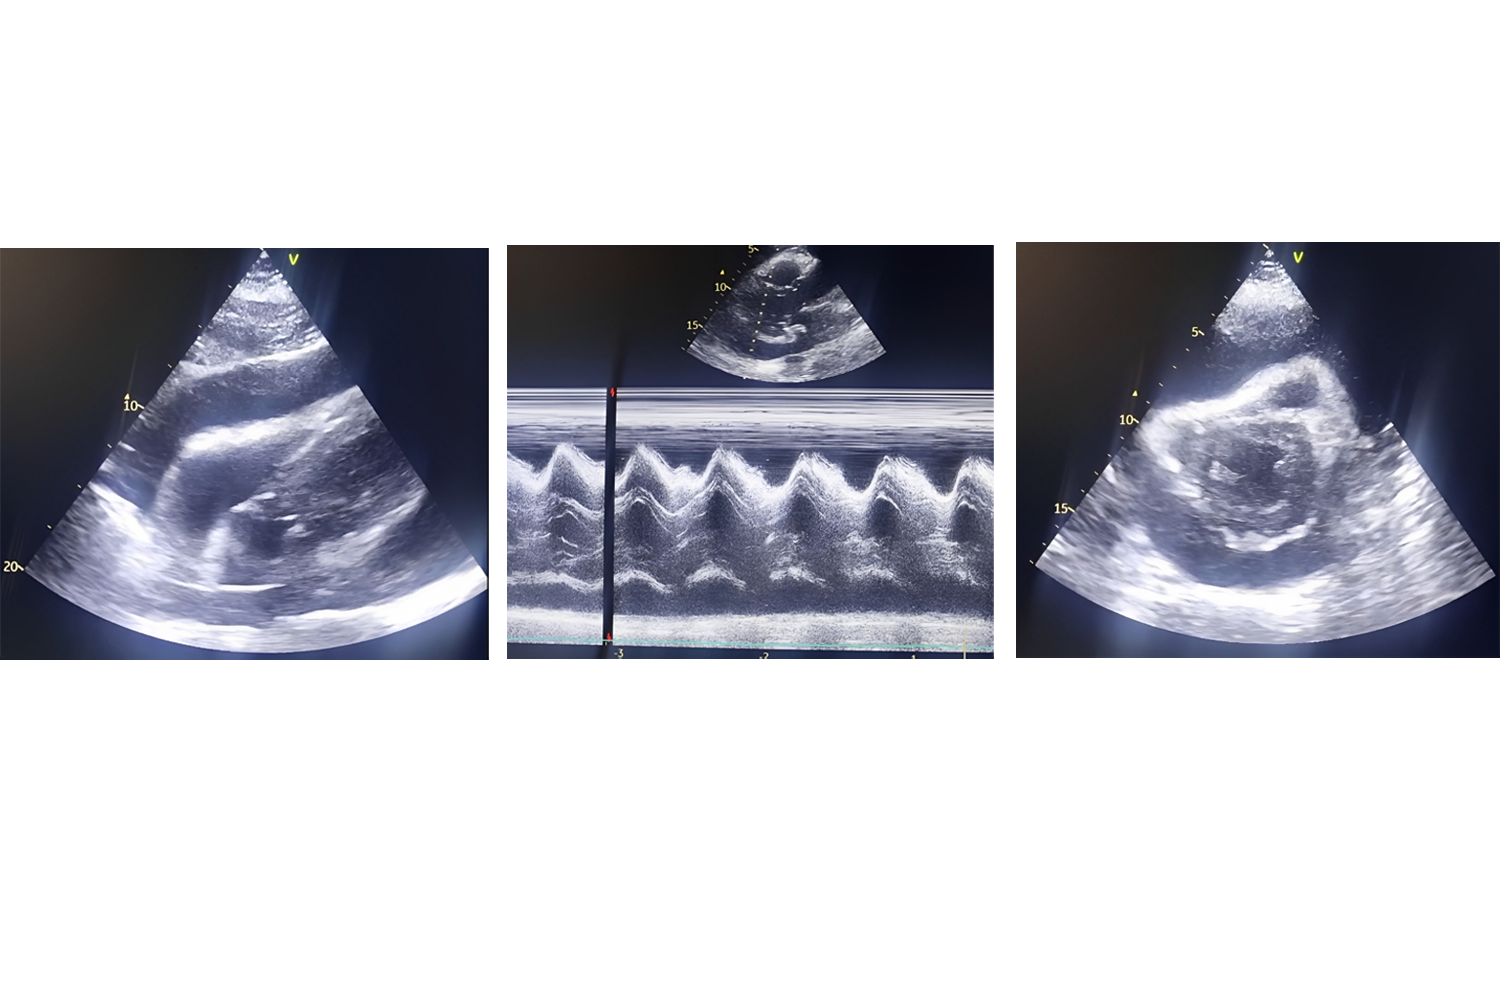

Image of the Week - 29 May 2024

Doctor Sofien Ayed